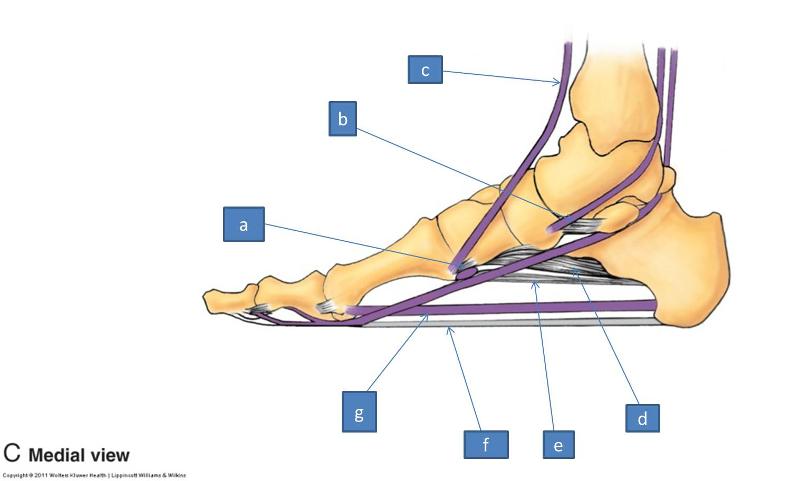

Анатомия голеностопа: Сухожилия и их строение